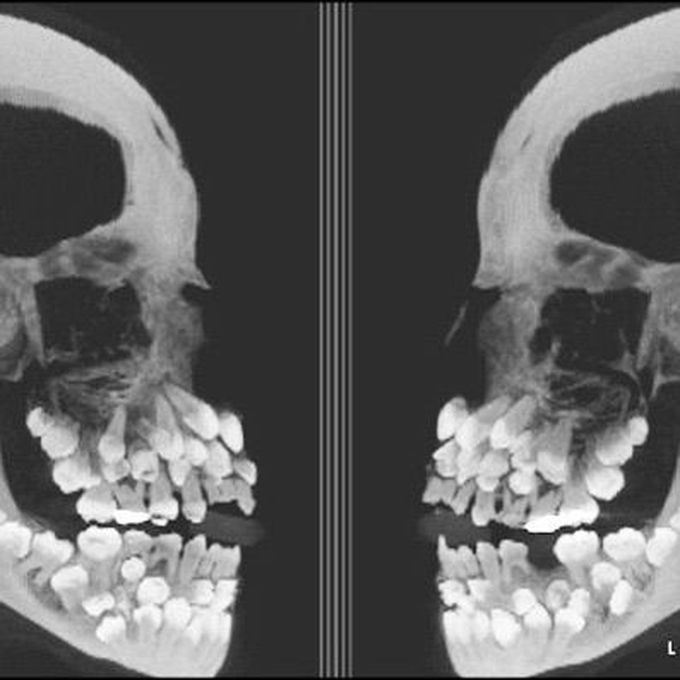

Hyperdontia

Supernumerary teeth